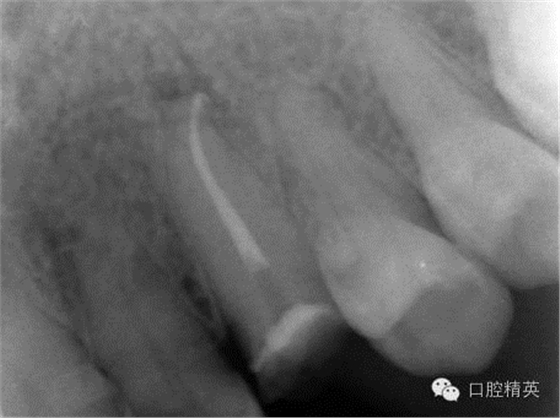

圖3 根管治療后X片